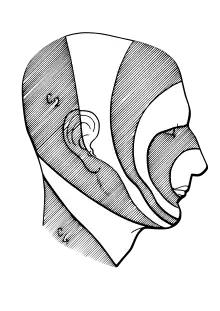

Dermatomes

The areas of cutaneous distribution (dermatomes) of the three sensory branches of the trigeminal nerve have sharp borders with relatively little overlap (unlike dermatomes in the rest of the body, which have considerable overlap). The injection of a local anesthetic, such as lidocaine, results in the complete loss of sensation from well-defined areas of the face and mouth. For example, teeth on one side of the jaw can be numbed by injecting the mandibular nerve. Occasionally, injury or disease processes may affect two (or all three) branches of the trigeminal nerve; in these cases, the involved branches may be termed:

Somatotopic representation

Exactly how pain-temperature fibers from the face are distributed to the spinal trigeminal nucleus is disputed. The present general understanding is that pain-temperature information from all areas of the human body is represented in the spinal cord and brainstem in an ascending, caudal-to-rostral fashion. Information from the lower extremities is represented in the lumbar cord, and that from the upper extremities in the thoracic cord. Information from the neck and the back of the head is represented in the cervical cord, and that from the face and mouth in the spinal trigeminal nucleus.

Within the spinal trigeminal nucleus, information is represented in a layered, or "onion-skin" fashion. The lowest levels of the nucleus (in the upper cervical cord and lower medulla) represent peripheral areas of the face (the scalp, ears and chin). Higher levels (in the upper medulla) represent central areas (nose, cheeks and lips). The highest levels (in the pons) represent the mouth, teeth and pharyngeal cavity.

The onion skin distribution differs from the dermatome distribution of the peripheral branches of the fifth nerve. Lesions which destroy lower areas of the spinal trigeminal nucleus (but spare higher areas) preserve pain-temperature sensation in the nose (V1), upper lip (V2) and mouth (V3) and remove pain-temperature sensation from the forehead (V1), cheeks (V2) and chin (V3). Although analgesia in this distribution is "nonphysiologic" in the traditional sense (because it crosses several dermatomes), this analgesia is found in humans after surgical sectioning of the spinal tract of the trigeminal nucleus.